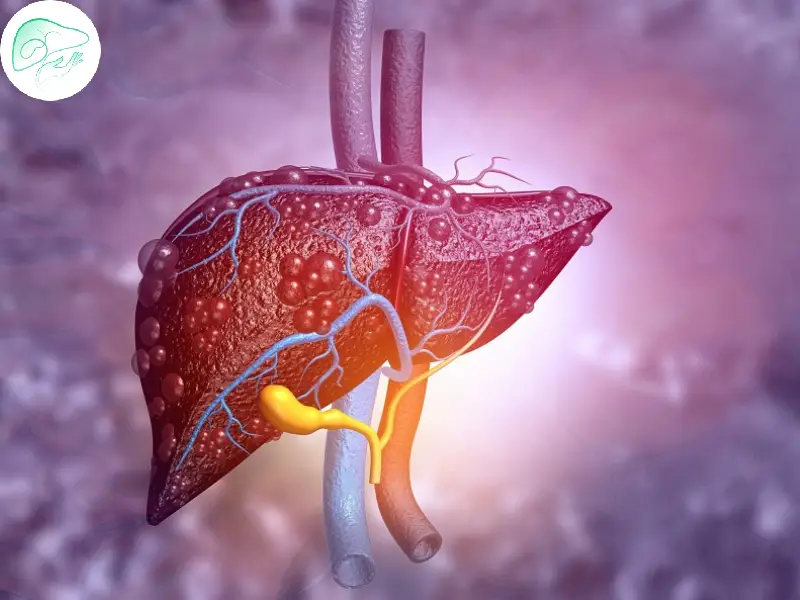

التلیّف الکبدی: تحذیر لصحه الکبد وطرق الوقایه والعلاج

لماذا یُعَدّ التلیّف الکبدی خطیرًا؟

یحدث التلیّف الکبدی عندما تُستبدَل أنسجه الکبد السلیمه بأنسجه ندبیه (تلیفیه) نتیجه الإصابات المتکرره أو الالتهابات. یمکن أن یؤدی هذا الأمر إلى اضطراب الوظائف الطبیعیه للکبد وزیاده خطر حدوث مشکلات خطیره مثل تشمّع الکبد، سرطان الکبد، أو حتى فشل الکبد الکامل.